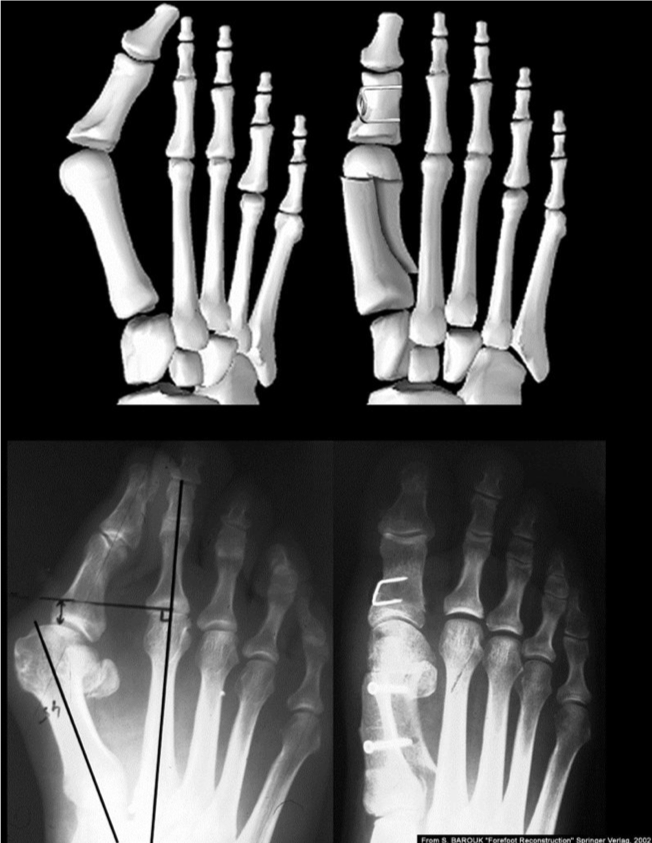

Hallux Valgus – Scarf osteotomy

Bone broken and shifted in the coronal plane

Hallux Valgus – basal osteotomy